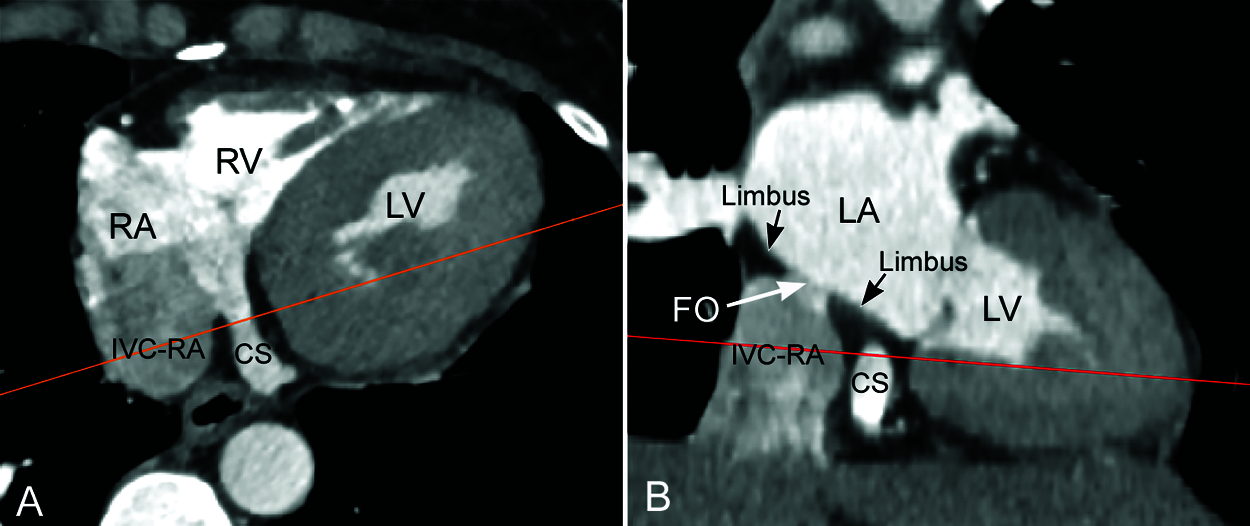

Figure 4: Computed tomographic angiograms along the long (A) and short (B) axes of the coronary sinus (CS) from the same patient shown in Fig. 3. Redlines indicate the imaging planes for the images in the other panel. The coronary sinus is surrounded by low density epicardial fat in this obese individual. Note that the epicardial fat extends into the adjacent limbus. FO, fossa ovalis; IVC-RA, inferior vena cava–right atrial junction; LA, left atrium; LV, left ventricle; RA, right atrium; RV, right ventricle